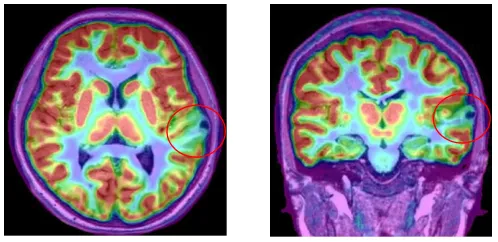

术前MRI

术前PET